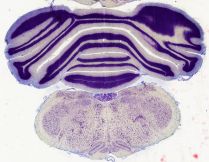

Datasets -> Rattus Norvegicus -> CV, (Cresyl Violet), coronal, histo, Whole-Brain, adult [ Metadata ]   ·   Source: R. Glenn Northcutt Collection, MCZ-Harvard   ·   [ R. Glenn Northcutt Collection info ]

| Displaying Sections 121 thru 138 of 138 Sections for this Dataset Pages:   1   2   3   4